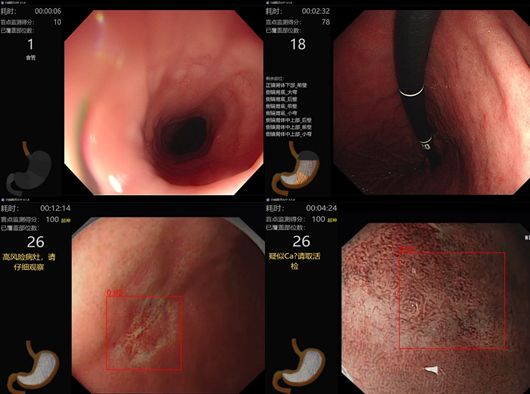

EndoAngel®产品的功能包括上消化道盲区监测、可疑病灶识别,下消化道退镜速度监测、回盲部位识别、息肉识别等。有了EndoAngel®的辅助,有望发现更多的消化道早癌。除以上功能外,我们还在不断追求新的突破,目前已启动研发早癌分化程度和边界预测、食管静脉曲张辅助诊断、实时肠道清洁度评估以及在胆胰EUS和ERCP中的应用。

EndoAngel®上消化道辅助监测(来源:Endoangel公众号)